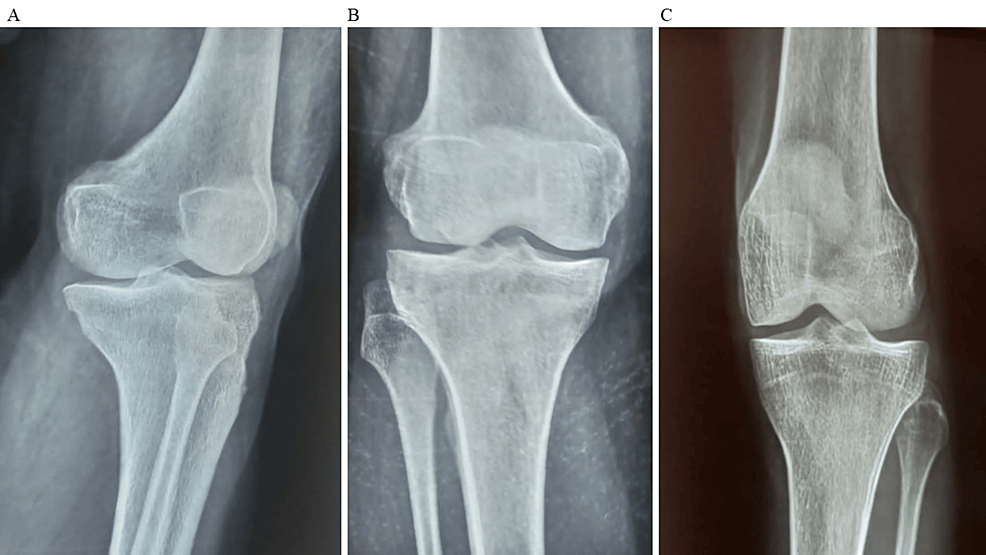

除了骨關(guān)節(jié)炎外,15名參與者還被發(fā)現(xiàn)患有骨缺損,占該隊(duì)列的30%。這些缺損包括各種情況,例如骨折、退行性骨病或先天性畸形,突顯了研究中涉及的骨科問題多種多樣。下圖1顯示了開始干細(xì)胞治療之前的骨骼側(cè)視圖和前后視圖。

圖1:顯示了開始干細(xì)胞治療之前的骨骼側(cè)視圖和前后視圖。

圖1:A:干細(xì)胞治療前(側(cè)視圖),B:干細(xì)胞治療前前后位(AP)視圖,C:干細(xì)胞治療前前后位(AP)視圖。